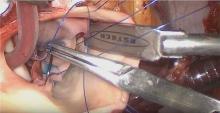

Methods: A 30-year-old man developed fever, new aortic insufficiency (AI), and positive blood cultures. After intravenous antibiotic therapy, the blood cultures cleared and aortic valve reconstruction was undertaken. The infection had caused thickening and defects in the fused leaflet of a Sievers Type 1 bicuspid valve, and the leaflets were not salvageable. After excision of the diseased cusps, 3 CardioCel leaflets were fashioned and sutured securely to the valve annulus, using Ozaki's technique. Good leaflet apposition was obtained.

Results: After discontinuing cardiopulmonary bypass, the reconstructed CardioCel leaflets moved well with complete competence, a coaptation height of greater than 1 cm, and a 7 mmHg mean systolic gradient. The patient recovered uneventfully with no complications. The patient remains asymptomatic with unchanged echo parameters and has returned to full work activity.